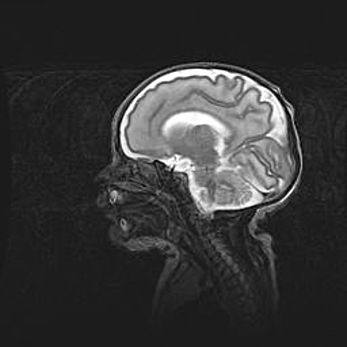

Церебральная ишемия II.

Возраст: 5 дней

Вес: 3400 г

Пол: женский

Окружность головы: 35 см

Срок гестации: 39 недель

Церебральная ишемия – это заболевание, характеризующееся недостаточностью (гипоксией) либо полным прекращением (аноксией) снабжения мозга кислородом по причине закупорки одного или нескольких сосудов. Это приводит к  что метаболическим расстройствам различной степени тяжести в тканях головного мозга, развитию коагуляционных некрозов и гибели нейронов.